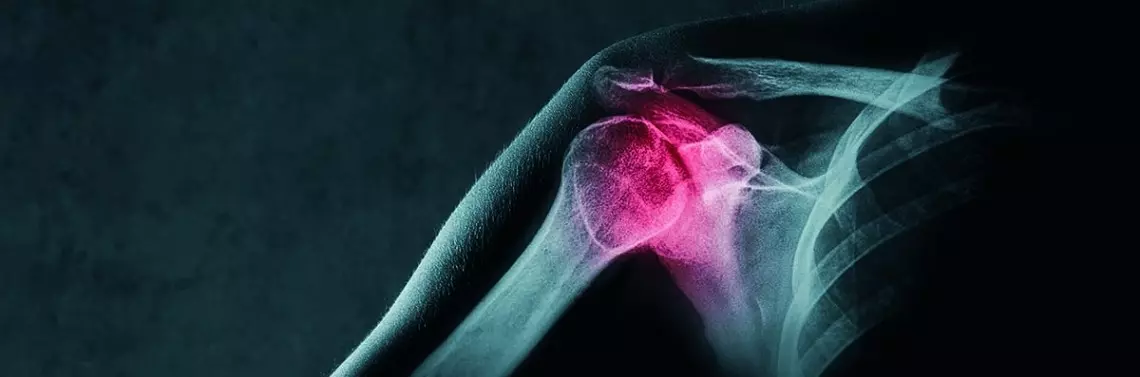

Anatomia stawu barkowego

Obręcz barkowa ma największy zakres ruchu ze wszystkich stawów [1]. Staw barkowy łączy kończynę górną z tułowiem. Opisywana struktura składa się z wielu elementów, które biorą udział w ruchu barku. Do składowych anatomicznych stawu barkowego zalicza się m.in. stawy: mostkowo-obojczykowy, barkowo-obojczykowy i ramienny.